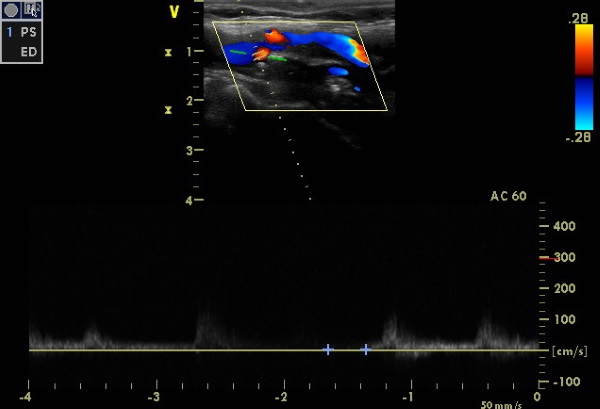

Допплерография

Применяется эффект Доплера. Волны отражаются от эритроцитов, что формирует изображение на экране. На этом изображении отображаются все сосуды с кровотоком.

Допплерография предоставляет возможность сканирования сосудов, по которым движется кровь.

Ультразвуковая допплерография (УЗДГ) выполняется двумя методами:

- Транскраниальный. Исследуется сосудистая система головы. Процедура осуществляется с помощью датчика, который размещается на области черепа с минимальной толщиной кости.

- Обследование экстракраниальных сосудов. Анализируются вены и артерии, расположенные в шее.

Допплерография представляет собой двухмерное исследование, позволяющее оценить кровоток в сосудах вне черепной коробки. Основным преимуществом УЗДГ является возможность раннего выявления различных патологий. Однако существует и недостаток: точное определение скорости кровотока не осуществляется.

Дуплексное сканирование

Этот метод исследования обладает большей глубиной по сравнению с допплерографией. Процедура позволяет получить цветное изображение сосудистых структур как внутри черепа, так и вне его. Такое сканирование назначается, когда диагноз уже установлен.

Триплексное сканирование

Это трехмерное ультразвуковое исследование, которое представляет собой современный метод диагностики сосудов головного мозга. В процессе процедуры объединяются дуплексное сканирование и анализ скоростей кровотока в сосудах с использованием цветового картирования.